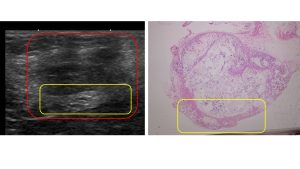

皮膚超音波検査では赤丸に包まれるやや低エコー性の境界明瞭な病変が観察される。黄色で包まれる底部では低エコーと連続する高エコーの領域が見られる。HE染色では低エコーの領域は脂肪組織で高エコーの領域は細胞成分が増している。細胞成分が増している領域は脂肪組織に対するマクロファージを主体とした肉芽腫性炎症が観察される。